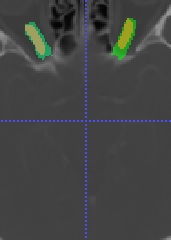

In Chapter 6, we propose an end-to-end, atlas-free 3D convolutional deep learning framework for fast and fully automated whole-volume HaN anatomy segmentation [115]. Our deep learning model, called AnatomyNet, segments OARs from head and neck CT images in an end-to-end fashion, receiving whole-volume HaN CT images as input and generating masks of all OARs of interest in one shot. AnatomyNet is built upon the popular 3D U-net architecture, but extends it in three important ways: 1) a new encoding scheme to allow auto-segmentation on whole-volume CT images instead of local patches or subsets of slices, 2) incorporating 3D squeeze-and-excitation residual blocks in encoding layers for better feature representation, and 3) a new loss function combining Dice scores and focal loss to facilitate the training of the neural model. These features are designed to address two main challenges in deep-learning-based HaN segmentation: a) segmenting small anatomies (i.e., optic chiasm and optic nerves) occupying only a few slices, and b) training with inconsistent data annotations with missing ground truth for some anatomical structures. We collect 261 HaN CT images to train AnatomyNet, and use MICCAI Head and Neck Auto Segmentation Challenge 2015 as a benchmark dataset to evaluate the performance of AnatomyNet. The objective is to segment nine anatomies: brain stem, chiasm, mandible, optic nerve left, optic nerve right, parotid gland left, parotid gland right, submandibular gland left, and submandibular gland right. Compared to previous state-of-the-art results from the MICCAI 2015 competition, AnatomyNet increases Dice similarity coefficient by 3.3% on average. AnatomyNet takes about 0.12 seconds to fully segment a head and neck CT image of dimension , significantly faster than previous methods. In addition, the model is able to process whole-volume CT images and delineate all OARs in one pass, requiring little pre- or post-processing. We demonstrate that our proposed model can improve segmentation accuracy and simplify the auto-segmentation pipeline. These contributions are released as an open-source software package called AnatomyNet, which is publicly available555https://github.com/wentaozhu/AnatomyNet-for-anatomical-segmentation. Portions of this chapter were published as part of [115].